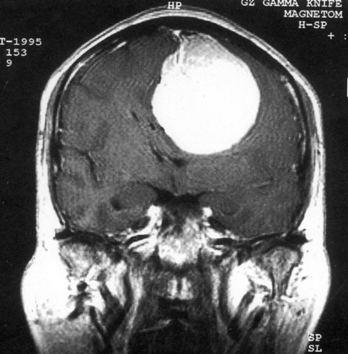

病历摘要:??患者女性,37岁。大便时突起炸裂样头痛3小时,伴喷射样呕吐。既往体健。体检:T37.5℃,BP145/90mmHg,R20次/分,P85次/...

问题 病历摘要:??患者女性,37岁。大便时突起炸裂样头痛3小时,伴喷射样呕吐。既往体健。体检:T37.5℃,BP145/90mmHg,R20次/分,P85次/分。神志清楚,颅神经检查无异常,颈强直,克、布氏征(-),四肢肌力、肌张力正常,病理征(-)。 为明确诊断,可考虑作什么检查?

选项 A.脑血管造影 B.TCD C.CTA D.MRA E.颅骨平片 F.诱发电位 G.PET H.SPECT I.脑磁图

答案 ACD